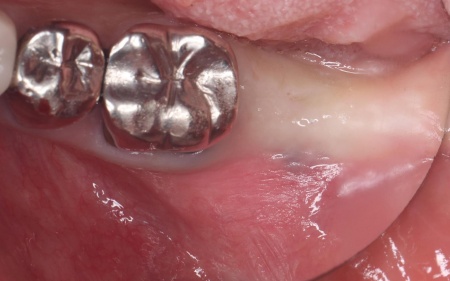

治療前

歯根破折が疑われました。